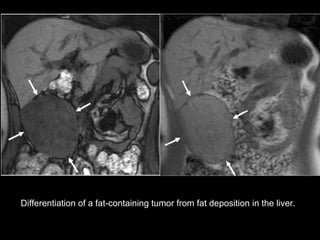

Fat-containing Primary Tumors Hepatic adenomas, hepatocellular carcinomas, and, rarely, focal nodular hyperplasias  may have microscopic fat content.  Hence, a finding of intralesional fat  does not help exclude these entities , and  clinical findings  as well as  imaging features  such as morphologic structure, mass effect, and enhancement characteristics must be considered.

Differentiation of a fat-containing tumor from fat deposition in the liver.

Fat-containing Primary TumorsHepatic adenomas, hepatocellular carcinomas, and, rarely, focal nodular hyperplasias may have microscopic fat content. Hence, a finding of intralesional fat does not help exclude these entities , and clinical findings as well as imaging features such as morphologic structure, mass effect, and enhancement characteristics must be considered.

Differentiation of afat-containing tumor from fat deposition in the liver.